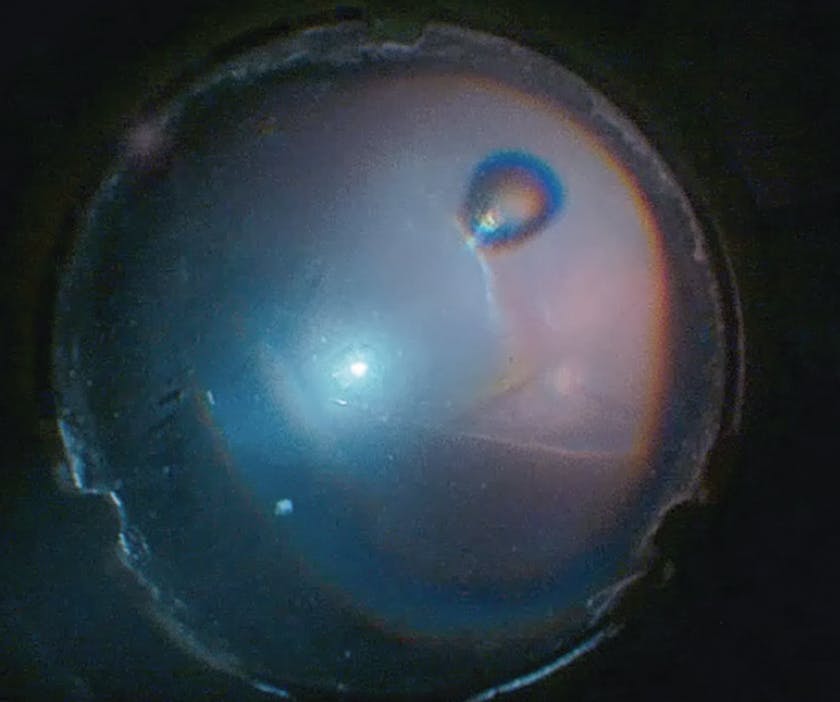

Figure 3. Wide-angle viewing system view under chandelier illumination shows area of retinal detachment involving macula.

Figure 4. Wide-angle viewing system view under chandelier illumination shows resolution of subretinal fluid after subretinal fluid drainage.